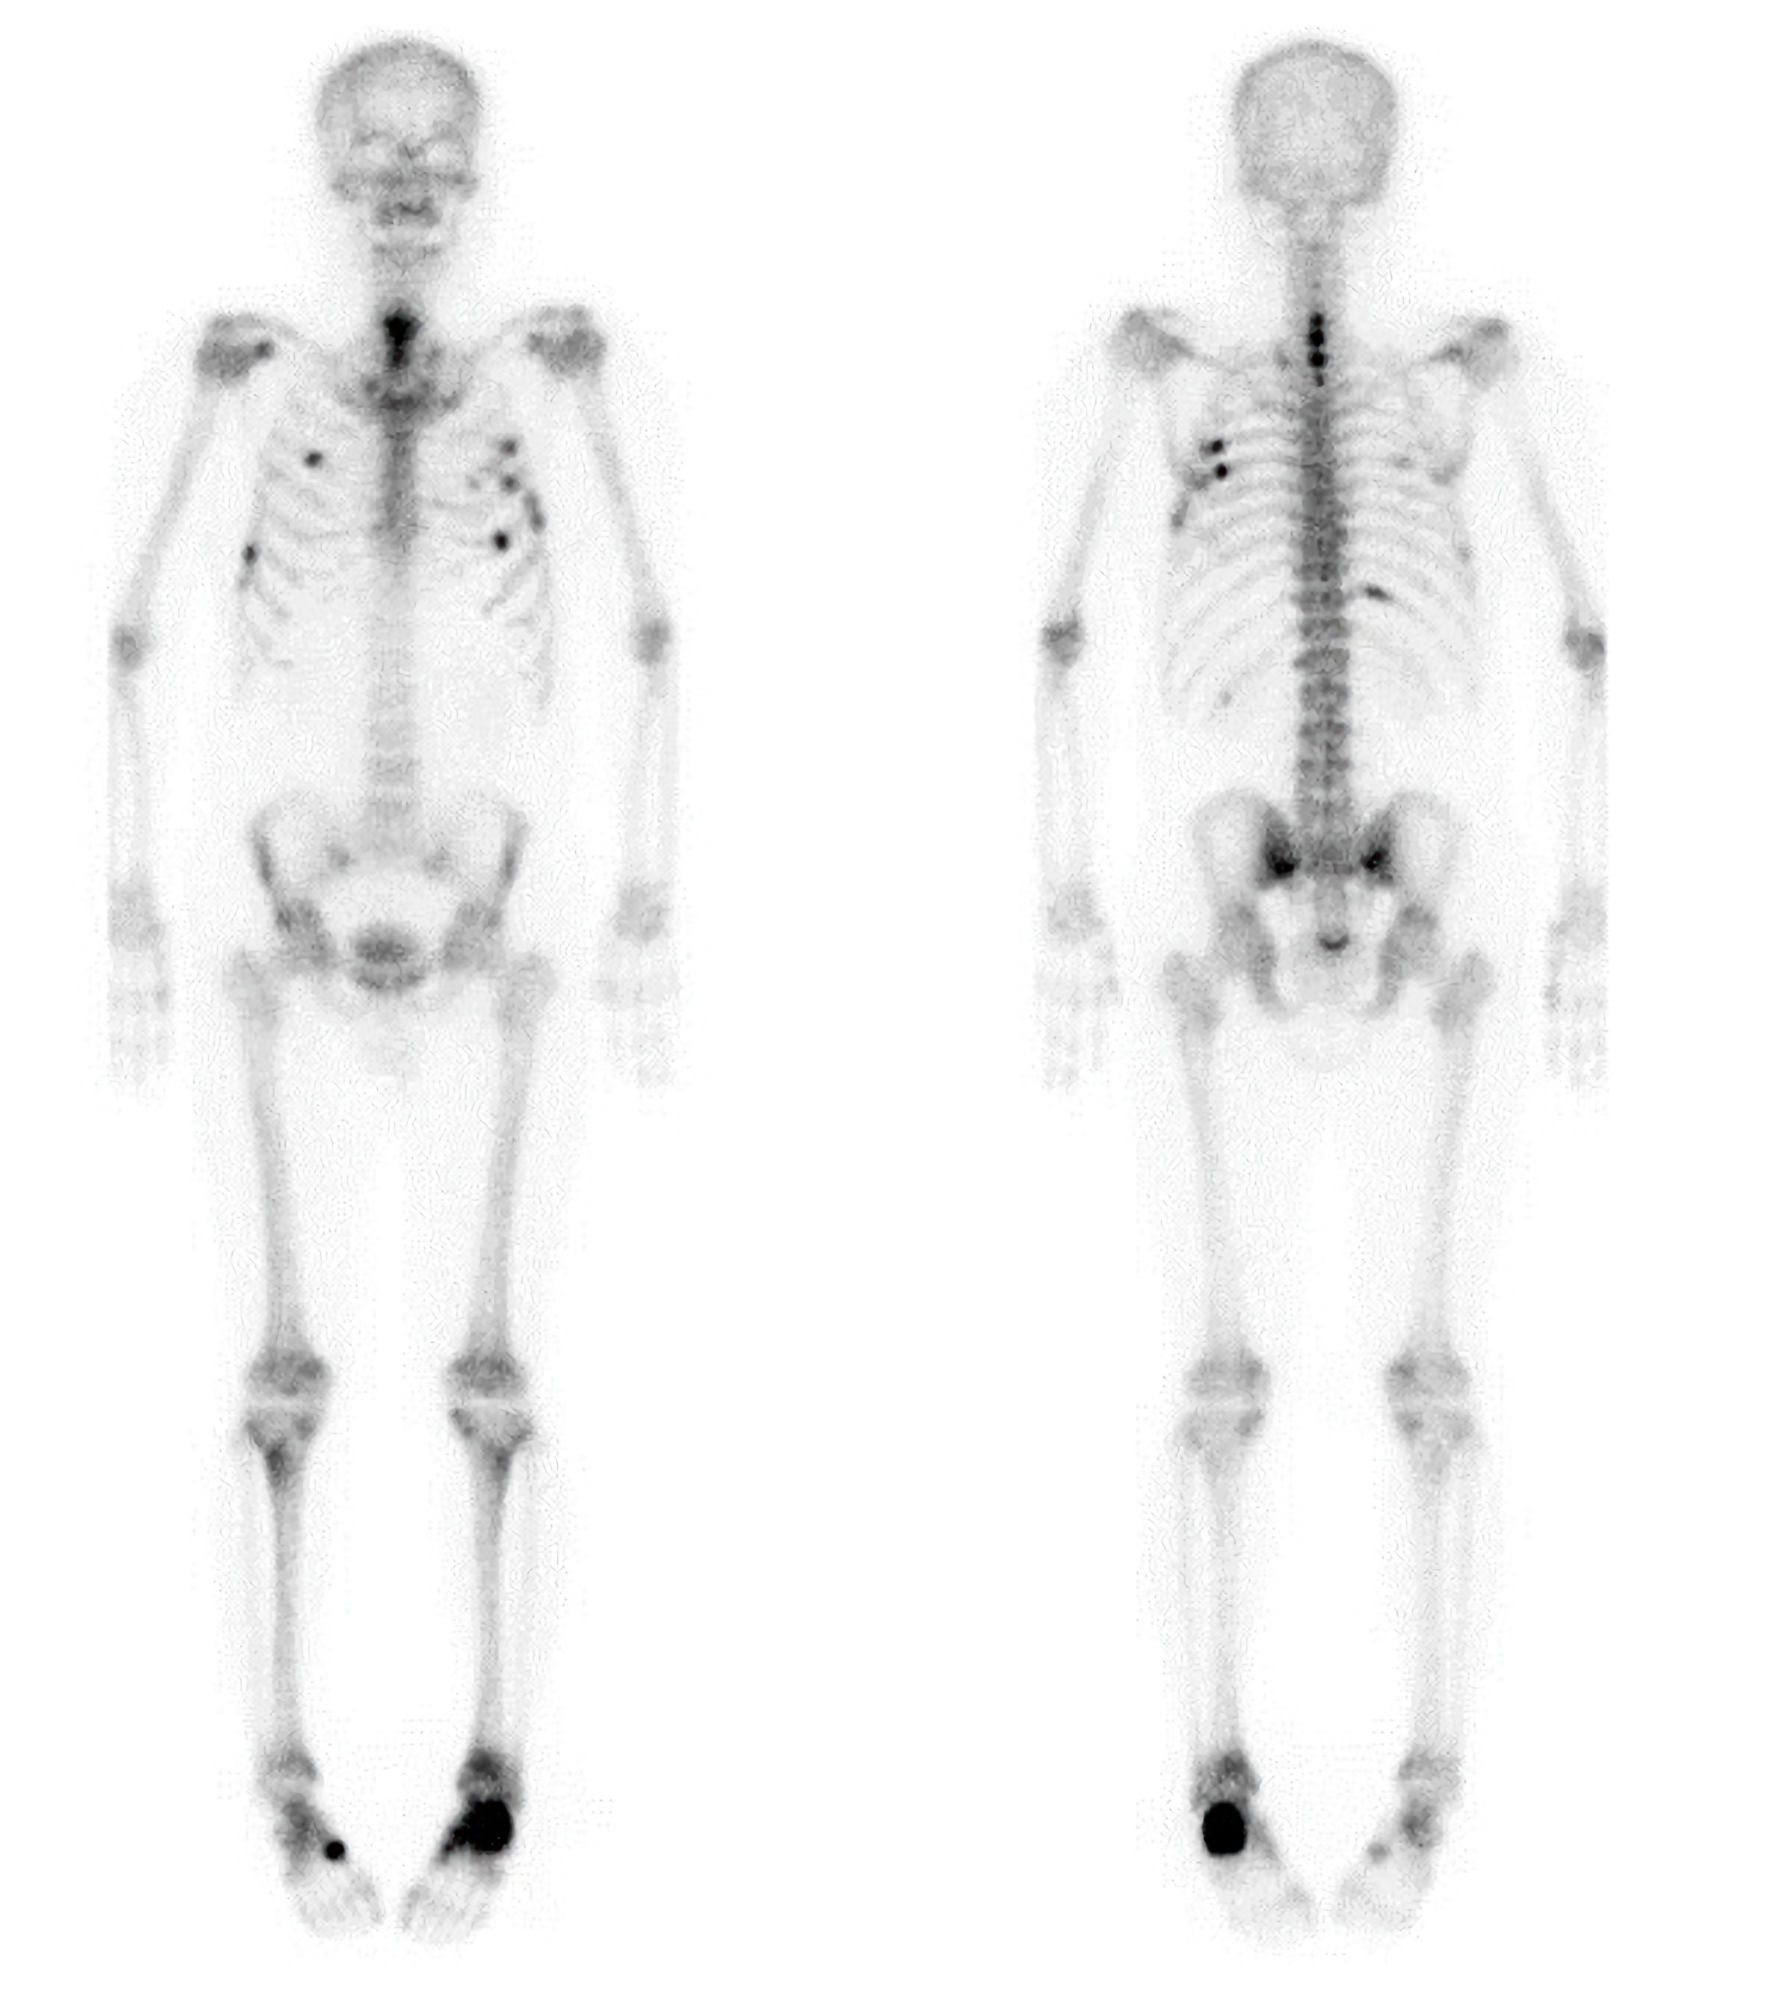

A 58-year-old man was referred to the Endocrinology Department in September 2022 for evaluation and treatment of very low bone mineral density (BMD) (T-score of −4.5 in the lumbar spine) and a 2-year history of bone pain involving both feet, the upper back, the left scapula, and the chest wall, without antecedent trauma. He had first been referred to the Orthopedic Department of our clinic in January 2021 because of left heel pain lasting 3 months, with magnetic resonance imaging (MRI) from another local clinic showing a fracture line along the physis of the calcaneal posterior tuberosity. The patient, a physician by occupation, had been walking about 10 km daily on his commute as exercise, until he stopped in October 2020 due to heel pain while walking. He also reported pain in the upper back and along the medial border of the left scapula for 1–2 years, which had been diagnosed as myofascial pain syndrome at another local clinic. On physical examination, there was mild tenderness over the posterior tuberosity of the left calcaneus with local warmth in the left heel, as well as tenderness along the medial border of the left scapula, with pain aggravated by abduction of the left arm. Plain radiographs of both feet, the scapula, and the spine demonstrated an incomplete or stress fracture in the posterior body of the left calcaneus, multiple rib fractures with immature callus formation in the left upper ribs, and mild degenerative changes with osteophytes, respectively. Whole-body bone scintigraphy using technetium-99m methylene diphosphonate (99mTc-MDP) revealed multiple areas of increased uptake along the anterior arcs of the right third and seventh ribs, posterior arcs of the right sixth and 11th ribs, anterolateral and posterior arcs of the left third to sixth ribs, the C5–T1 spine, the left calcaneal area, the right midfoot, and the lower sacral region, suggesting multiple fractures or possible bone metastases (Fig. 1). Cervical spine MRI demonstrated fracture healing of the C6–T2 spinous processes with callus formation. The patient’s serum ALP level was elevated, with an increased bone fraction. Extensive malignancy workup—including blood tests (tumor markers and protein electrophoresis), urine protein electrophoresis, positron emission tomography–computed tomography, chest and abdominal computed tomography, and esophagogastroduodenoscopy—was negative. Thereafter, his left heel pain improved, but he developed pain in the right heel. Bilateral foot MRI performed in August 2022 at a local clinic showed healing of the left calcaneus and a stress fracture in the right calcaneus, findings suggestive of metabolic bone disease. Laboratory results from the same clinic 1 month before presentation (August 2022) were as follows: serum ALP 297 U/L (reference 40–129; 81.7% bone fraction), ionized calcium 1.0 mmol/L (1.10–1.34), intact parathyroid hormone (PTH) 34.1 pg/mL (15.0–65.0), 25-hydroxyvitamin D (25(OH)D) 20.7 ng/mL (vitamin D insufficiency 10.0–30.0), procollagen type 1 N-terminal propeptide (P1NP) 86 ng/mL (22.9–85.3), C-terminal telopeptide of type 1 collagen (CTx) 1.190 ng/mL (0.161–0.737), hemoglobin A1c 6.0%, and lumbar spine BMD T-score −4.5 (L1–4). Thyroid hormone, cortisol, testosterone, complete blood count, and liver and renal function tests were within normal limits, except for low uric acid. Urinalysis revealed protein 2+ and glucose 4+.

Figure 1. Whole-body bone scintigraphy showing multiple areas of increased radiotracer uptake involving the anterior arcs of the right third and seventh ribs, the posterior arcs of the right sixth and 11th ribs, the anterolateral and posterior arcs of the left third through sixth ribs, the C5–T1 spine, the left calcaneus, the right midfoot, and the lower sacral region.